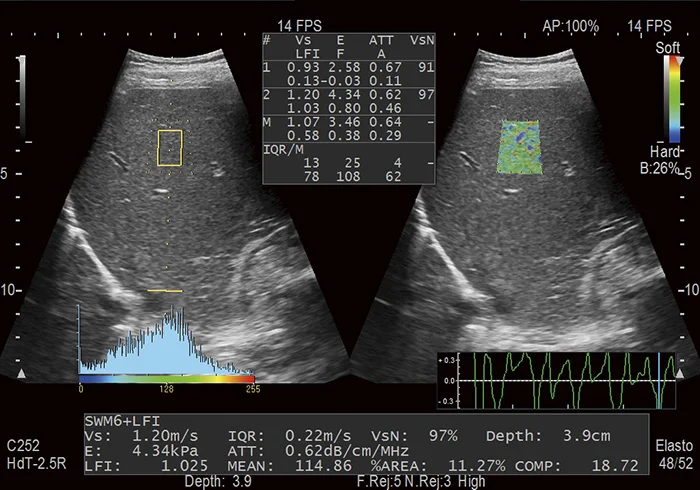

Combi-Elasto - комплексное исследование эластичности ткани печени

На сегодняшний день предлагается совместное применение эластографии и эластометрии при исследовании печени - комплексная технология Combi-Elasto.

Эластография является неинвазивным методом диагностики фиброза печени. При таком исследовании компрессия тканей печени осуществляется с помощью передаточной пульсации от сердечных сокращений. Таким образом исключается необходимость приложения ручной компрессии. Важным вспомогательным инструментом здесь является гистограмма эластичности тканей в выбранной зоне интереса: она не только графически отображает распределение жесткостей, но и позволяет вычислить количественный индекс для стадирования фиброза - LF Index. Корреляция между индексом LF Index и степенью фиброза подтверждена с помощью мультицентровых апробаций.

В методике эластометрии главным измеряемым параметром является скорость распространения сдвиговой волны, которая напрямую зависит от жёсткости ткани. В свою очередь, жёсткость ткани зависит от степени фиброза.

Оба метода доступны на одном датчике, что исключает необходимость смены датчиков во время процедуры. Комбинированный подход призван повысить эффективность диагностики за счёт предоставления дополнительных данных.